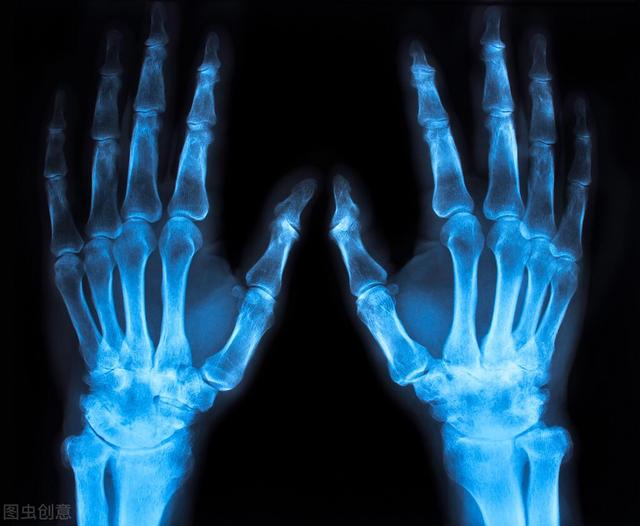

类风湿性关节炎是一种非常常见的、全身的、慢性的自身免疫性疾病,40岁以后高发,是致残率非常高的一种关节炎,常累及身上的一些小关节,尤其是掌指关节、近端指间关节、腕关节。

患上类风湿性关节炎后,早期,患者多表现为关节游走性疼痛、肿胀和功能障碍,等到了晚期,患者会出现明显的关节僵硬、畸形、骨骼肌萎缩,甚至还可能出现心、肺、肾、周围神经及眼的内脏病变。

(5)手部X光片有典型的囊性骨侵蚀,关节面模糊,关节间隙狭窄。